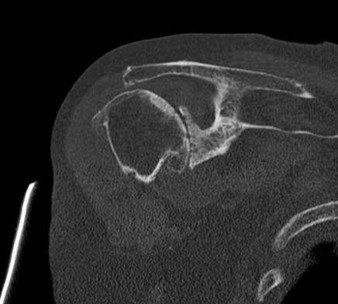

Question 32:

A 28-year-old male presents after an unprovoked seizure. He complains of right shoulder pain and is unable to externally rotate his arm. Imaging confirms a posterior shoulder dislocation. Further evaluation reveals an impaction fracture of the humeral head known as a reverse Hill-Sachs lesion. Where is this articular defect classically located?

Correct Answer: Anteromedial aspect of the humeral head

Explanation:

A posterior shoulder dislocation commonly results in an impaction fracture of the humeral head as it is driven against the posterior glenoid rim. This defect is known as a reverse Hill-Sachs lesion and is classically located on the anteromedial aspect of the humeral head. In contrast, an anterior dislocation produces a standard Hill-Sachs lesion, which is located on the posterolateral aspect of the humeral head.